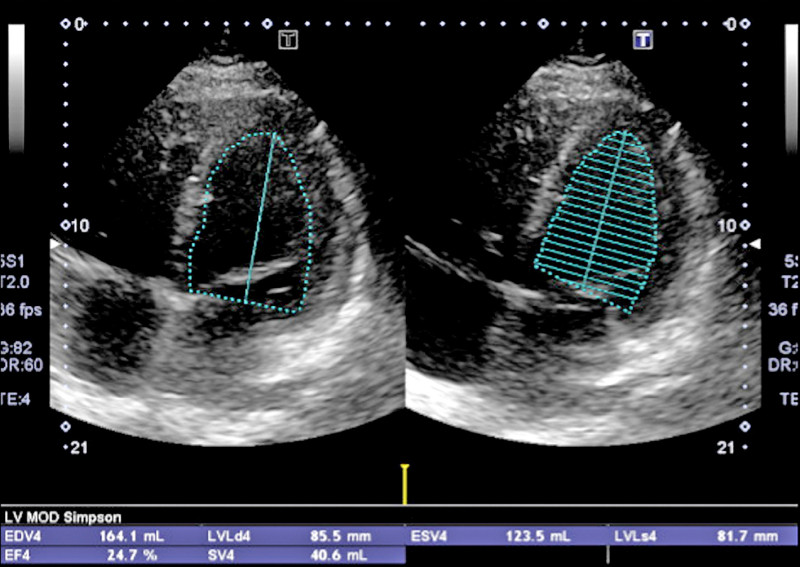

44歲李先生正值壯年,卻喘到爬不了樓梯、雙腳嚴重水腫,甚至1個多月都得「坐著睡覺」,就醫檢查,竟是左心室收縮率僅剩25%的嚴重心臟衰竭。所幸,透過包含新型「排糖藥」(SGLT2抑制劑)在內的「黃金四本柱」治療後,症狀大幅改善,也恢復生活品質。不過李先生相當疑惑:「醫師,我又沒有糖尿病,為什麼要吃排糖藥?」

一般健康的心臟,左心室收縮率(LVEF)在50-55%以上,一旦降至35%以下,就是醫學定義的嚴重心臟衰竭。經心臟超音波檢查發現,李先生的左心室收縮率(LVEF)只剩下25%,情況相當不樂觀。